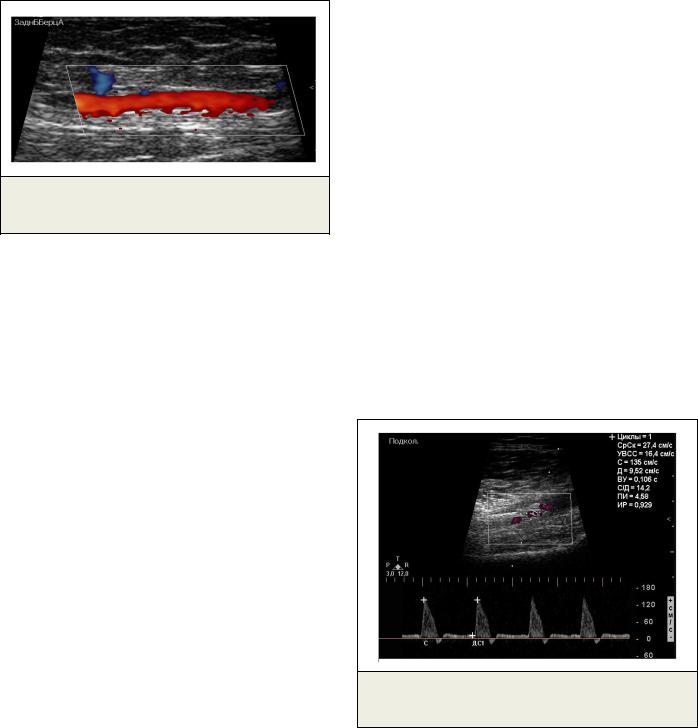

Рис. 7. УЗДС. Режим ЭДК.

Бедренно-подколенный шунт.

По данным ультразвукового дуплексного сканирования бедренно-подколенный шунт проходим (Рис. 7). В области дистального анастомоза визуализируется стент, в подколенной артерии также визуализируется стент, ультразвуковых признаков стенозов in-stent не выявлено, кровоток в подколенной артерии маги- стрально-измененного типа (Рис. 8). Задняя большеберцовая артерия проходима, кровоток магистрально-измененного типа (Рис. 9, Рис.